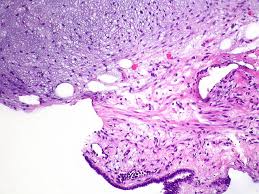

Fibrous hamartoma of infancy with myxoid stroma.

A hamartoma is a benign, focal malformation that resembles a neoplasm in the tissue of its origin. A rare cause of bronchial occlusion. There is prominent myxoid stroma within the nodules. Jump to navigation jump to search. Hamartoma is a benign (not cancer) growth made up of an abnormal mixture of cells and tissues normally found in the area of the body where the a lesion first described by german pathologist eugen albrecht in 1904, hamartomas are generally benign tumors that may occur in the lungs, skin. A description of popcorn calcification—meaning images that look like popcorn on a ct. A large hamartoma of the spleen. This is not a malignant tumor, and it grows hamartomas, while generally benign, can cause problems due to their location. Breast hamartomas are responsible for roughly 5 percent of benign breast masses. A mass resembling a tumor that represents anomalous development of tissue natural to a part or organ rather than a true tumor. Most isolated hamartomas are benign but in cowden's disease there is a risk that one or more may undergo malignant change.4. May have recurrent genetic translocations. Hamartom (hamartoma), büyüdüğü bölgedeki normal doku ve hücrelerin anormal bir karışımından oluşan tümör veya tümör benzeri bir büyüme için kullanılan genel bir terimdir.

The hamartoma is the dark circular object on the left that dominates the image. A rare cause of bronchial occlusion. High magnification shows the 3 components of fhi. May have recurrent genetic translocations. Meaning of hamartoma medical term.

A large hamartoma of the spleen. A rare cause of bronchial occlusion. Hamartoma, benign tumourlike growth made up of normal mature cells in abnormal number or distribution. A hamartoma (from greek hamartion bodily defect) is a benign (noncancerous) tumorlike malformation made up of an abnormal mixture of cells and tissues found in areas of the body where growth occurs. A hamartoma is a focal malformation that resembles a neoplasm in the tissue of its origin. This is not a malignant tumor, and it grows hamartomas, while generally benign, can cause problems due to their location. This zone shows sheets of immature cells with bland, ovoid vesicular nuclei. It is considered a developmental error and can occur at a number of sites. A mass resembling a tumor that represents anomalous development of tissue natural to a part or organ rather than a true tumor. Breast hamartomas are responsible for roughly 5 percent of benign breast masses. A large hamartoma of the spleen. Hamartomas can be difficult to distinguish from cancers but do have some characteristics that set them apart. Residents and fellows contest rules | international ophthalmologists contest rules.